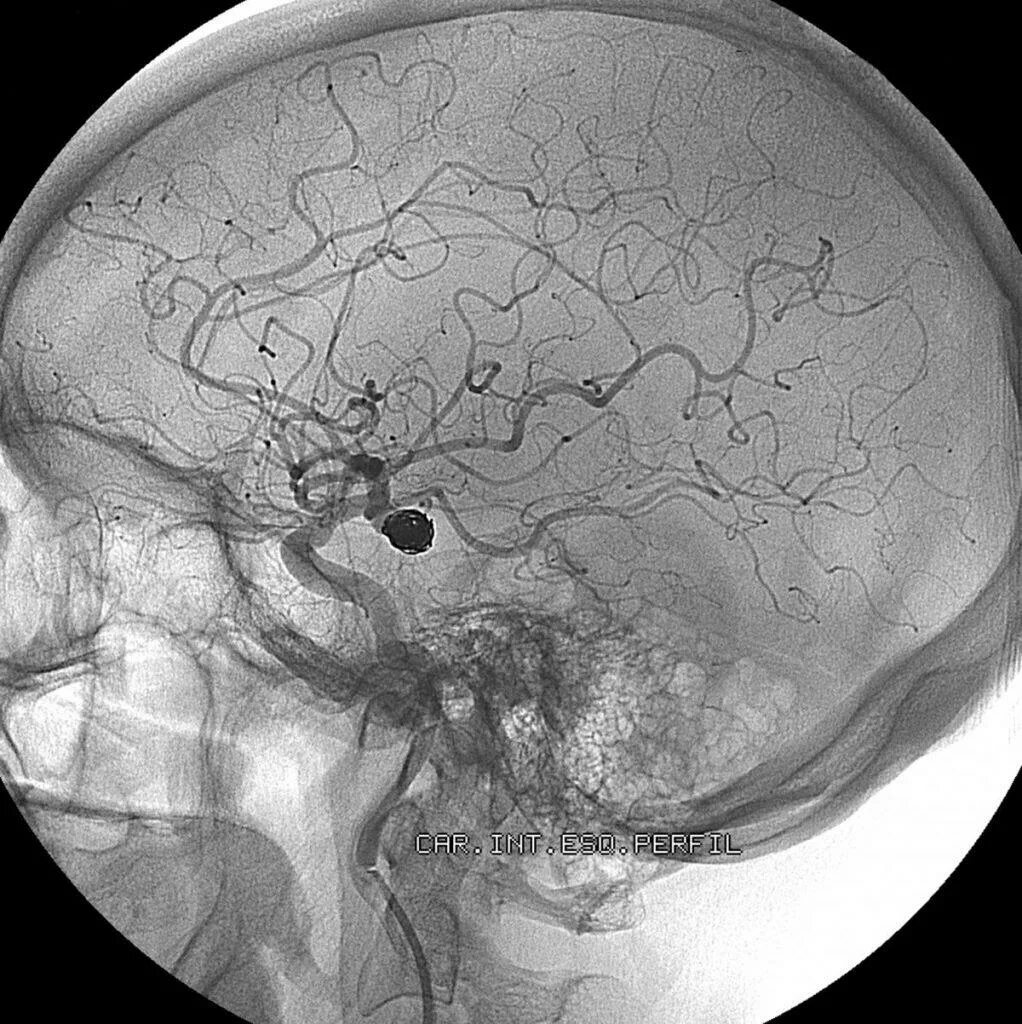

Аневризма сосудов мозга симптомы